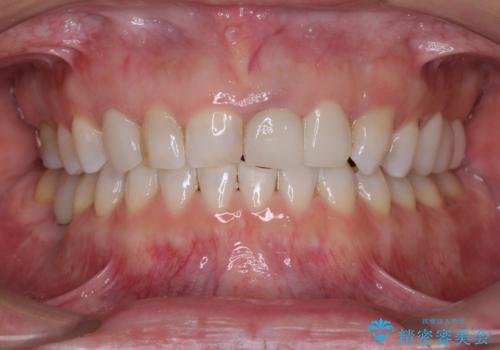

[ 前歯開咬 ] 前歯が噛んでいない マウスピース矯正治療

担当医 大元洋佑

![[ 前歯開咬 ] 前歯が噛んでいない マウスピース矯正治療の症例 治療後](https://seimitsushinbi.jp/wp/wp-content/uploads/2022/11/IMG_2488-500x350.jpg?v=1668218373)